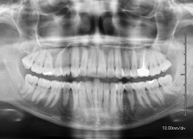

- RX Ortopantomografía (RX Panorámica dental)

Técnica mediante la cual, utilizando rayos X, se obtienen imágenes de ambos maxilares y de las piezas dentarias para su estudio. Indicaciones: piezas dentales retenidas, estudio de ortodoncia, estudio de implantes dentales.